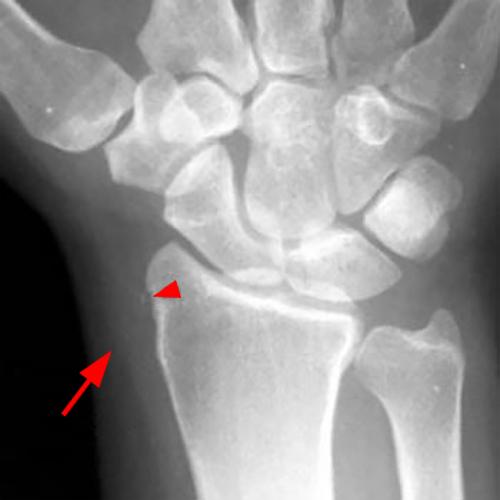

Radiography: Radiographs are not the primary imaging modality for diagnosing DQT, but they can suggest chronic inflammation in the first dorsal compartment by revealing focal cortical erosion, sclerosis, or periosteal bone apposition of the radial styloid sheath, along with overlying soft tissue swelling (Figure 6).28 These findings, though nonspecific, may support a clinical diagnosis of DQT. However, the absence of these findings on radiographs does not rule out the condition.

Figure 6: A 53-year-old female with radial-sided wrist pain for 4 months. A postero-anterior wrist radiograph demonstrates plain film changes of de Quervain's tenosynovitis. The radial styloid demonstrates subtle periosteal bony apposition (arrowhead), and adjacent soft tissue swelling is evident (arrow). Axial fat-suppressed proton-density image from the same patient demonstrates peritendinous edema (blue arrowhead), mild tendon enlargement (arrow), and reactive marrow edema of the radius (red arrowheads).